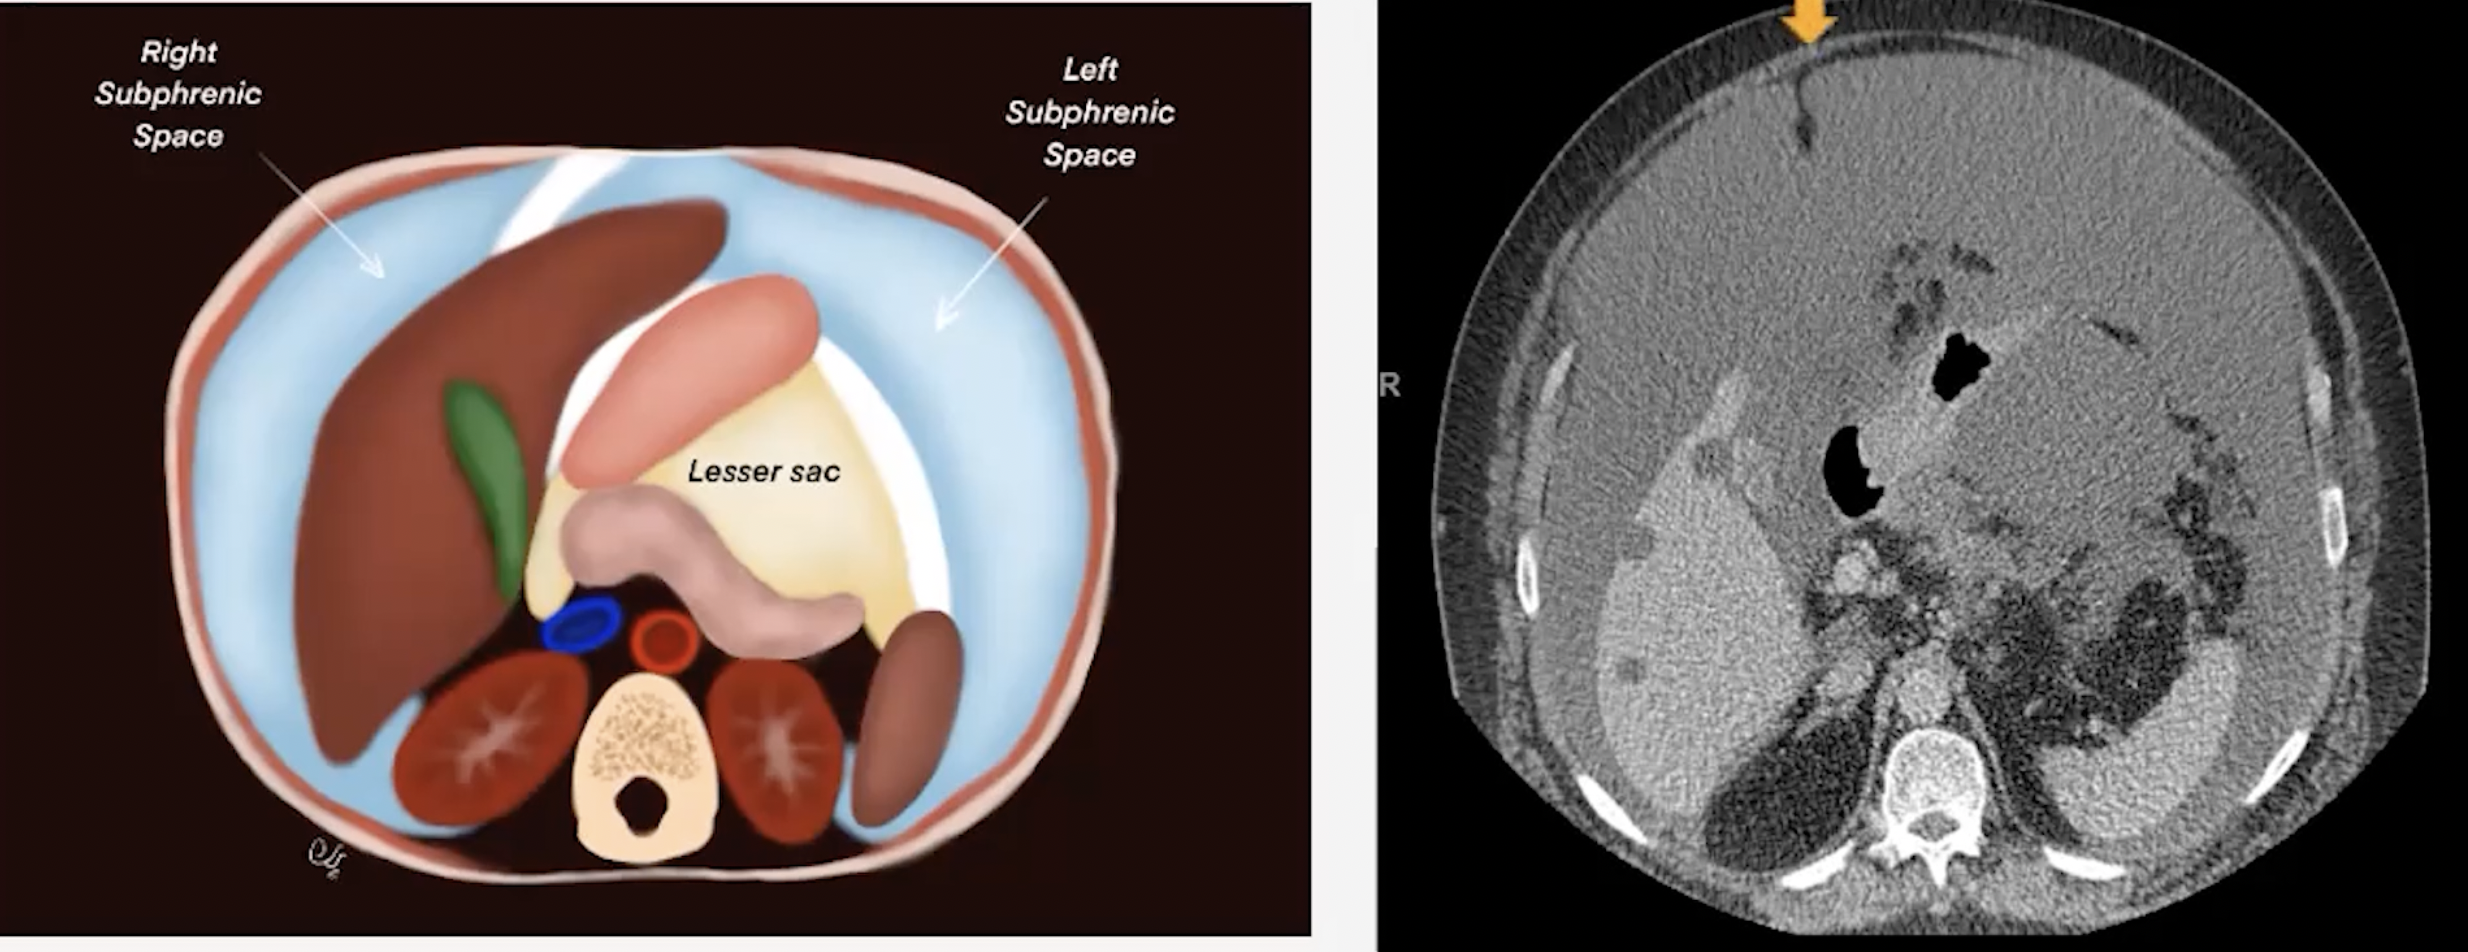

• Falciform ligament

• Separates the right and left subphrenic spaces

• Connects peritoneum to diaphragm

• Lesser Sac